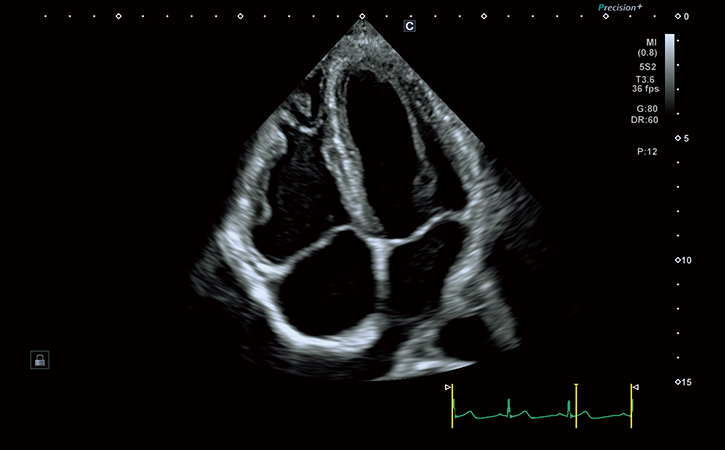

心エコー

- 心臓の動きや弁の状態

- 心不全・弁膜症の評価